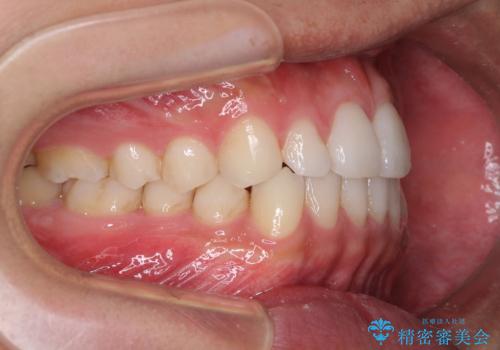

前歯のデコボコとクロスバイト インビザライン矯正治療

- 前歯のデコボコとクロスバイトを治したいとのことで来院された患者様です。

上下顎ともに歯列全体の側方拡大を行い、下顎前歯はIPR(歯と歯の間を削る)によってデコボコとクロスバイトが解消するように設計し、インビザラインにより治療を行うこととしました。

2年弱で終了する予定でしたが、途中来院されなかった時期があり、その後舌側転位している前歯を動かせるところまで動かしたいとのことで4年ほど治療を継続されました。